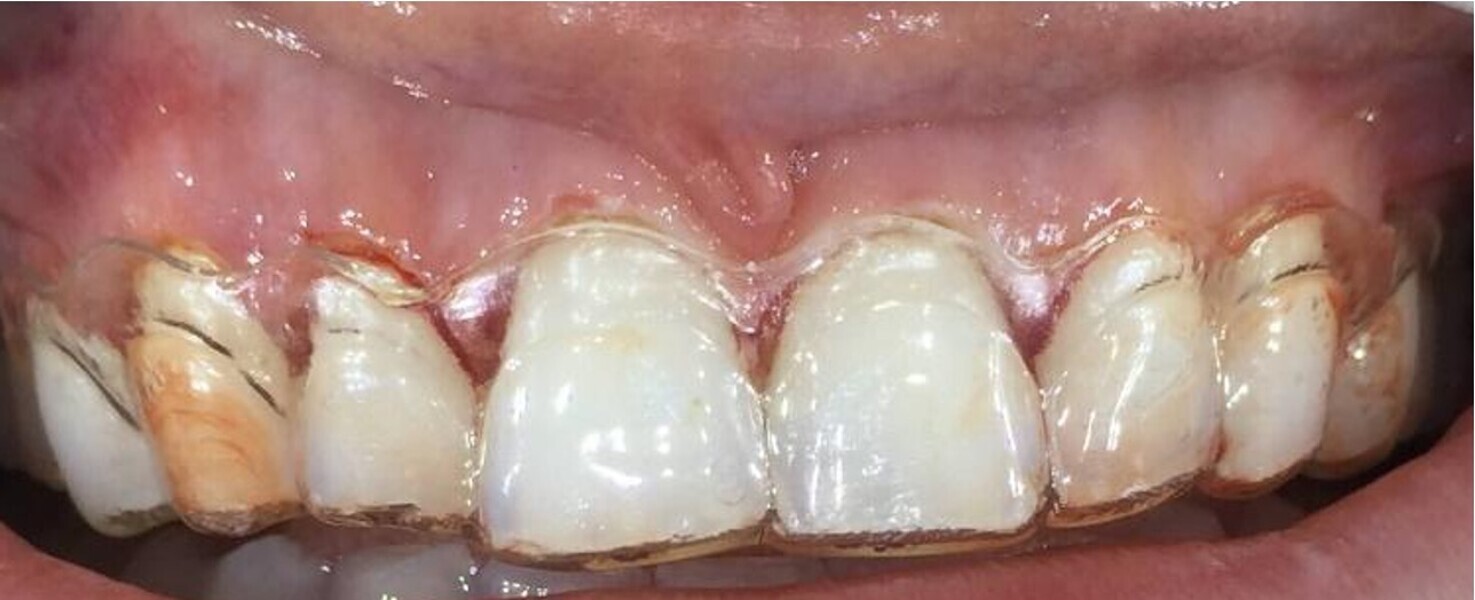

This first case was a female patient in her twenties wanting to improve her smile. She had a traumatic anterior crossbite with dentinal and enamel fractures on teeth #11, 21, 31 and 41. She had received a plan elsewhere for veneers as her only option. I decided to use the clear aligner software to demonstrate what was possible and then demonstrate her restorative options using VISS. Furthermore, to be transparent with the patient, we decided to simulate the restorative solution before aligner treatment to assist and educate the patient on what it would look and feel like.

This powerful visualisation tool (Figs. 32–34) creates the best-informed consent for the patient and protects the clinician by demonstrating the true differences and consequences of both scenarios and risks. The patient can see the difference in tooth preparation required and therefore the consequences and risk associated with it. This approach trumps any verbal consent or generic brochure available.

The patient, based on the VISS simulation, decided to undergo Invisalign treatment, which lasted for ten months. Her choice of direct or indirect restoration was then rediscussed, and we decided on Philips in-chair whitening and IPS e.max veneers (Ivoclar) on the six maxillary anterior teeth and the mandibular central incisors (Figs. 35–37).